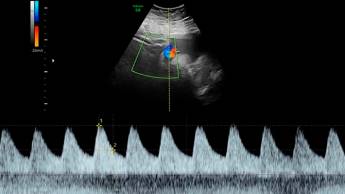

- Сделать УЗИ. Ультразвуковое сканирование — безопасный и очень информативный метод. Он не несет угрозы ни будущей матери, ни ребенку, но при этом позволяет не только подтвердить факт беременности, но и выявить патологии, например внематочную беременность или анэмбрионию — отсутствие зародыша в плодном яйце.

УЗИ можно делать с третьей недели — исследование на этом сроке позволит подтвердить беременность, но более информативным оно будет в конце первого триместра — в это время можно оценить специфику развития плода, увидеть отклонения, задержки, а также патологии со стороны мамы.